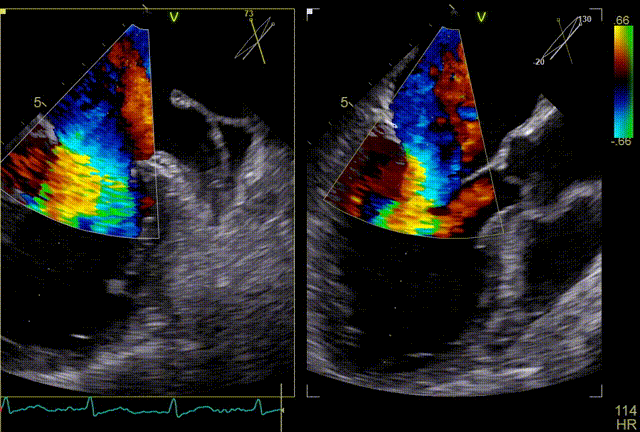

在食道超声王蓓主任的紧密配合下,经食道超声引导后傅国胜教授使用二尖瓣夹准确成功捕获前叶A2和后叶P2反流最严重区域,并予夹合,使二尖瓣在收缩期由大的单孔变成小的双孔,显著减少了二尖瓣反流。

反复测试二尖瓣钳夹的稳定性,超声复查提示二尖瓣夹内侧反流有效改善,外侧仍有部分反流,平均跨瓣压差2mmHg,肺静脉收缩期逆流频谱恢复正向,傅国胜教授团队与超声影像团队充分沟通讨论,计划在二尖瓣夹外侧再置入第二枚二尖瓣夹,遂精准释放第一个二尖瓣夹。

再次反复测试第二枚二尖瓣钳夹的稳定性,超声复查提示二尖瓣反流明显改善,平均跨瓣压差4mmHg。